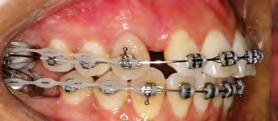

en paciente adulto tratado con extracciones de primeros molares permanentes. Reporte de caso

Dentista y Paciente 52 Sonriendo al futuro

Extraer los primeros molares permanentes puede ser una opción de tratamiento en ciertos casos de ortodoncia, como aquellos con apiñamiento moderado, biprotrusión, mordidas abiertas, o problemas de clase II y III que requieran extracciones. Además, se considera esta opción cuando los primeros molares están afectados por caries extensas u otras afecciones, lo que los hace más adecuados para la extracción y evita tratamientos restaurativos extensos o la necesidad de implantes en el futuro. Este artículo presenta el caso de una paciente en el que se optó por extraer los primeros molares superiores e inferiores para lograr resultados clínicos óptimos tanto en términos faciales como oclusales.

Palabras clave: extracción, primer molar, maloclusion, tratamiento ortodoncia.

Las extracciones dentales en los tratamientos de ortodoncia pueden ser indicadas en casos de caries extensas, restauraciones deficientes y/o extensas en premolares sanos, patologías periapicales, apiñamiento posterior y mordidas abiertas anteriores. La extracción de primeros molares permanentes es uno de los muchos planes de tratamiento en algunos casos de ortodoncia, en los cuales se presentan situaciones donde los primeros molares se encuentran comprometidos por lesiones cariosas extensas o alteraciones del desarrollo, por lo cual pueden ser candidatos para ser extraídos en casos donde se realizará tratamiento ortodóntico de pacientes como en los que se presentan apiñamiento moderado, biprotrusión, mordidas abiertas, clase II y III, casos en los cuales es necesario realizar exodoncias. Las extracciones posteriores producen una rotación antihoraria mandibular lo que podría ser conveniente en pacientes cuyas características faciales no se deben comprometer, como en pacientes con ángulo nasolabial obtuso, donde una significativa retracción de los dientes anteriores podría causar mayor apertura de este, lo que representaría en un resultado estético negativo y en camuflaje de pacientes clase II esqueléticas (extracciones superiores) y III (extracciones inferiores).1

189. Mayo 2024 53 Tratamiento ortodóncico

Cerrillo Lara Daniel. Ibarra Ramiro Jaime Tadeo. José de Jesús Anaya. Universidad Autónoma de Baja California. Campus Tijuana. Especialidad en Ortodoncia

Reporte del caso

Paciente del sexo femenino de 39 años de edad, sin datos patológicos aparentes, acude a la clínica de ortodoncia de la Facultad de Odontología campus Tijuana en diciembre del 2016. Su motivo de consulta fue: "Tengo el diente de abajo mal acomodado" En las fotografías extraorales se observa un paciente mesomorfo, biotipo mesoprosopo, línea superciliar asimétrica, línea bipupilar simétrica, nariz asimétrica, línea comisural asimétrica, labios medianos, tercio inferior aumentado respecto al medio y superior. Presenta perfil convexo, con un ángulo nasolabial obtuso (100°), surco mentolabial (122°). Línea dental superior desviada hacia la izquierda con respecto a línea media facial, muestra 100% de coronas dentales al sonreír. En el análisis intraoral se observa dentición permanente, líneas medias no coincidentes, microfracturas de OD #11 Y #21, clase molar indeterminada bilateralmente por ausencia de OD #16 Y #26, clase I canina bilateral, forma de arcada ovoide en superior, apiñamiento leve, #11, #12, #21 mesiorotados y #25 distorotado, forma de arcada ovoide en inferior, apiñamiento leve y OD #41 lingualizado, presencia de torus mandibular. Sobremordida horizontal de 2 mm y vertical de 20%. En el análisis radiográfico se muestran 26 dientes presentes en boca, ausencia de OD #16 y #26, presencia de #18, #28, #38 y #48 retenidos, altura de ramas mandibulares simétricas, densidad ósea

uniforme, relación corona-raíz 1:1; se observa además una maloclusión clase II esquelética, con crecimiento vertical, dientes anteroinferiores proinclinados así como los anterosuperiores.

Objetivos del tratamiento

Mejorar perfil del paciente, lograr clase molar I bilateralmente con mesialización de #37 y #47, después de extraer primeros molares mandibulares, mantener clase I canina bilateralmente, así como las sobremordidas vertical y horizontal, eliminar apiñamiento, corregir líneas medias, obtener oclusión funcional.

Plan de tratamiento interdisciplinario

Se remite al área de cirugía de la facultad de Odontología para extracciones de los OD #36 y #46 con el fin de armonizar la arcada inferior con la arcada superior, para después proceder a la mesialización de OD #37 y #47.

Plan de tratamiento ortodóncico

Se colocó aparatología fija superior e inferior tipo Alexander slot 0.022, se prosiguió a la alineación y nivelación, expansión superior e inferior con secuencias de arcos, mesialización de OD #37 y #47, recontorneo interproximal inferior, torque de raíces, armonización de arcadas, extracción de terceros molares inferiores y valoración de los superiores, retención removible superior e inferior.

Dentista y Paciente 54 Sonriendo al futuro

Figura 1. Fotografías extraorales de frente y de perfil. Figura 2. Fotografías intraorales iniciales.

Resultados

Se obtuvieron los resultados mencionados al inicio como clase I molar y canina, sobremordidas adecuadas, eliminación del apiñamiento, corrección de líneas medias y una oclusión funcional.

Discusión

La prevalencia de las extracciones dentales en los tratamientos de ortodoncia ha variado a lo largo de los años y esto es corroborado por 40 años de estudios retrospectivos llevados por Proffit, quien demuestra que durante los años 50 el porcentaje de

extracciones aumentó en un 10%, en los 60 en un 50 % y para los años 80 observó una reducción del 35%, al igual que para Peck y Peck que fue del 32% en ambos arcos.2-3

La extracción de algún diente siempre ha sido tema de discusión y aún más cuando son extracciones de primeros molares, ya que en un tratamiento por lo regular se considera que estos órganos dentarios son llaves fundamentales de la oclusión; sin embargo, Pérez en 2015 afirma que el tratamiento con extracciones de primeros molares tiene resultados positivos en el perfil, tal como

189. Mayo 2����2�� 55 Tratamiento ortodóncico

Figura 3. Modelos de estudio iniciales. Figura 4. Ortopantomografia inicial. Figura 5. Figura 6. Fase de alineación y nivelación.

sucedió en este caso y los reportados por Bahoquez en 2015. Rey en 2012 menciona también aquí resultados favorables al extraer los primeros 4 primeros molares a pesar de ser considerados piezas claves en la oclusión.4-5

Conclusión

La extracción de los primeros molares se presenta como una alternativa

efectiva para abordar casos de mordida abierta esquelética, perfiles convexos, rotación horaria de mandíbula entre otros, logrando resultados estables, funcionales y estéticamente satisfactorios. Es crucial destacar que esta decisión terapéutica requiere una cuidadosa elección de casos, así como una habilidad clínica y experiencia considerable para asegurar que las expectativas y resultados del tratamiento no se vean comprometidos.6

Dentista y Paciente 56 Sonriendo al futuro

Figura 7. Cierre de espacios superior e inferior. Figura 8. Retracción del segmento anterior. Figura 9. Fotografias intraorales finales.

Referencias

1. Rey D, Oberti G, Sierra A. Extraccion del primer molar permanente como una alternativa en el tratamiento de ortodoncia. Rev. CES Odont. 2012;25(1) 44-53.

2. Proffit WR. Forty-year review of extraction frequencies at a university orthodontic clinic. Angle Orthod. 1994;64(6):407–14.

3. Peck S, Peck H. Frequency of tooth extraction in orthodontic treatment. Am J Orthod. 1979 nov;76(5):491–6.

4. G. (2015). Tratamiento de mordida abierta con extracciones de primeros molares. Reporte de caso. Revista Mexicana de Ortodoncia, 3(4), 266–273.

5. Bahoquez, A. (2015). Exodoncias de primeros molares y verticalización de tercer molar inferior en paciente con mordida abierta, reporte de caso. Revista Latinoamericana de Ortodoncia y Odontopediatria.

6. Seddon JL. Extraction of four first molars: a case for a general practitioner? J Orthod. 2004 jun; 31(2):80-5.

7. Daugaard-Jensen I. Extraction of first molars in discrepancy cases. Am J Orthod. 1973 ago;64(2):115– 36.

8. Williams R. Single arch extraction--upper first molars or what to do when nonextraction treatment fails. Am J Orthod. 1979 oct;76(4):376–93.

189. Mayo 2����2�� 57 Tratamiento ortodóncico

Figura 10. Fotografias intraorales finales. Figura 11. Radiografía lateral de cráneo final. Figura 12. Fotografias extraorales finales.

Mucho cuidado con los equipos de rayos X intraorales portátiles

¿Está justificada esta advertencia?

Dentista y Paciente 58 Boletín

La redacción

En Dentista y Paciente queremos que los odontólogos conozcan el riesgo que implica el uso indebido de fuentes de radiación ionizante.

Los equipos portátiles están diseñados para llevar a cabo una exposición con el operador sujetando el equipo con ambas manos, y debido a la imposibilidad de alejarse del mismo a la distancia reglamentada, el operador se encontrará expuesto a una dosis de radiación ionizante once veces mayor, siendo esto el mejor de los casos.

Estamos conscientes de que la mayoría de los odontólogos ignoran los riesgos que implica el uso de fuentes de radiación, los cuales aumentan con la frecuencia y dosis de la misma, es por eso que nuestro deber nos llama a advertir al odontólogo para prevenir antes que lamentar.

En la literatura sobre la seguridad radiológica con equipos intraorales portátiles, hemos observado un creciente número de opiniones negativas sobre el uso de equipos diseñados para que el operador los sujete con sus manos para poder llevar a cabo así, una toma radiográfica periapical.

Esto implica que, de utilizarse el equipo portátil en el consultorio dental, el odontólogo tendrá en sus manos la fuente generadora de radiación, algo

189. Mayo 2024 59 Mucho cuidado con los equipos de rayos X intraorales portátiles

que no estaba previsto en la Norma Reguladora de Seguridad Radiológica NOM-229-SSA1-2002 (https:// www.gob.mx/cms/uploads/attachment/file/839898/IB_NOM229_ Infografia_24-03-2023_light.pdf), misma que excluyó de su campo de aplicación los equipos de rayos X convencionales, por considerar que los equipos de rayos X periapicales fijos tradicionales no presentarían mayores riesgos sanitarios al ser utilizados con los protocolos de seguridad sugeridos por ALARA, ICRP y otras instituciones, mismas que recomiendan mantener una distancia mínima de 2 metros entre el operador y la fuente generadora de rayos X, al efectuar el disparo mediante un disparador con cable retráctil, o con la opción de instalar un disparador remoto fuera del cuarto radiográfico.

Muchos odontólogos ignoran o subestiman los daños de tipo determinísticos o estocásticos, que son los causantes de provocar alteraciones cromosómicas a la célula, esto debido al uso indebido de fuentes

Muchos odontólogos ignoran o subestiman los daños de tipo determinísticos o estocásticos, que son los causantes de provocar alteraciones cromosómicas a la célula, esto debido al uso indebido de fuentes generadoras de radiación ionizante, pues aquellos que no lo saben suelen considerar al equipo portátil un avance tecnológico, cuando en realidad estos productos fueron diseñados para otras aplicaciones, al considerar que en sus países de origen su uso en el consultorio dental está restringido por normas de seguridad radiológica, debido a la imposibilidad para el operador de alejarse de la fuente de radiación, exponiéndose así a una dosis de radiación ionizante, por radiación dispersa y de fuga, mucho mayor de la que recibiría con un equipo fijo tradicional, al aplicar los protocolos antes mencionados.

Dentista y Paciente 60 Boletín

En la literatura sobre la seguridad radiológica con equipos intraorales portátiles, hemos observado un creciente número de opiniones negativas sobre el uso de equipos diseñados para que el operador los sujete con sus manos para poder llevar a cabo así, una toma radiográ����ca periapical��

1. RAGGI X IN MEDICINA-FISICA- TECNICA-APPLICAZIONI. Ed. GILARDONI S.p.A. 2.1.4.

2. ODOVTOS – Actualización en equipos de Rayos X portátiles en odontología. Lucía Barba Ramírez DDS, Deivi Cascante Sequeira DDS. Publicado en línea : 15-II-2021. Recuperado de: https://www.scielo.sa.cr/pdf/odovtos/v24n2/2215-3411-odovtos- 24-02-26.pdf

3. Revisión de las principales normas de protección radiológica para el uso de equipos de Rayos-X en odontología. Recuperado de: https://revistas.cientifica.edu.pe/index.php/ odontologica/article/download/538/6 19/